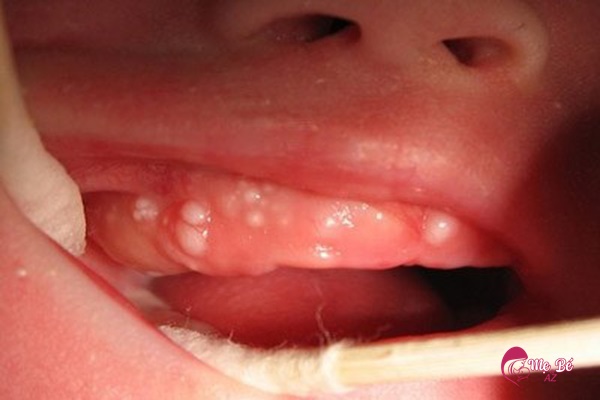

“Nanh sữa” là những nang nhỏ màu trắng đục hoặc vàng nhạt xuất hiện trên lợi của trẻ, thường gặp ở trẻ từ 0-3 tháng tuổi. Đây là tổn thương lành tính phổ biến ở niêm mạc miệng trẻ sơ sinh.

Kích thước nanh sữa thường chỉ khoảng 2-3mm, hiếm khi nào lớn tới 1cm.